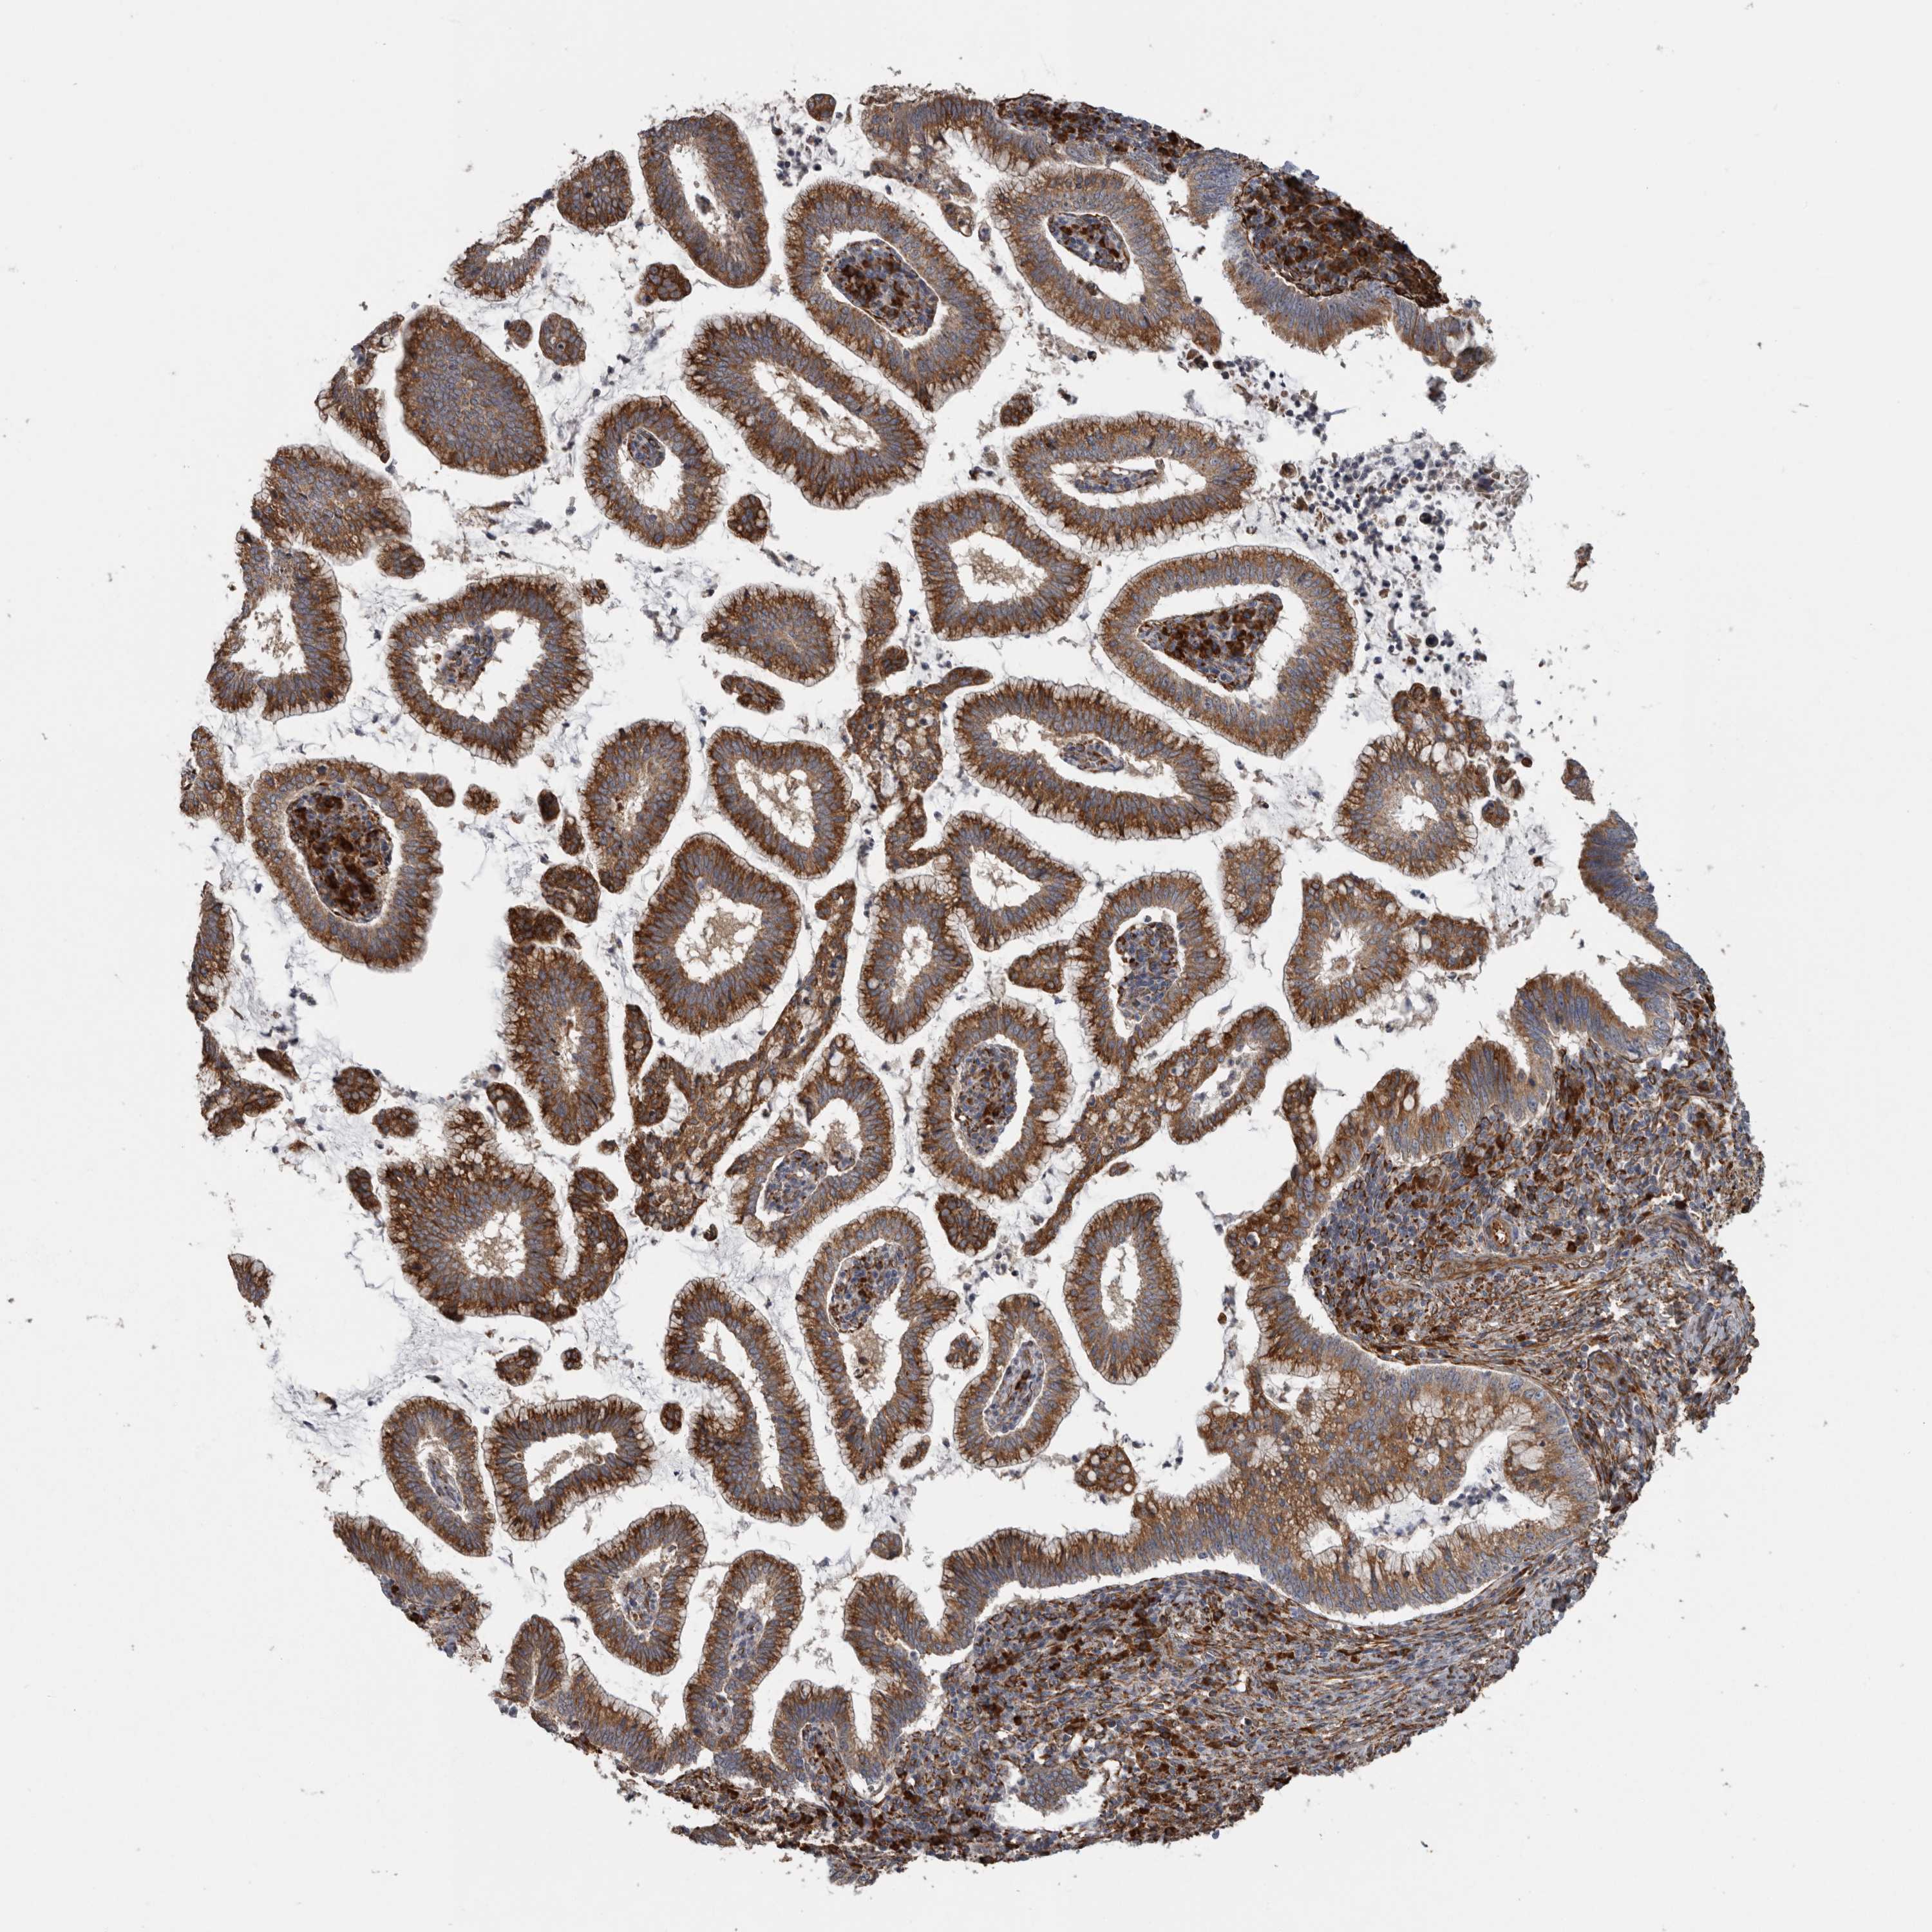

CERVICAL CANCER - Protein expressioni

A mouse-over function shows sample information and annotation data. Click on an image to view it in a full screen mode. Samples can be filtered based on level of antibody staining by selecting one or several of the following categories: high, medium, low and not detected. The assay and annotation is described here.

Antibody stainingi

Antibody staining in the annotated cell types in the current human tissue is reported as not detected, low, medium, or high, based on conventional immunohistochemistry profiling in selected tissues. This score is based on the combination of the staining intensity and fraction of stained cells.

Each image is clickable and will lead to virtual microscopy that enables deeper exploration of all samples and also displays staining intensity scores, fraction scores and subcellular localization as well as patient and tissue information for each sample.

Antibody HPA028355

Squamous cell carcinoma, NOS